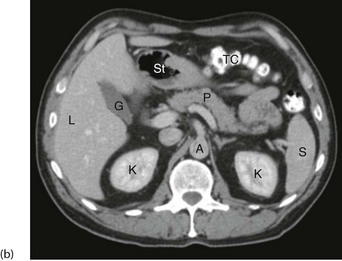

General principles of CT scanning: Computerised tomography involves X-raying a series of thin transverse ‘slices’ of the patient's head, body or limbs. A precise fan-shaped beam of X-rays is repeatedly pulsed from successive angles around the circumference of each slice and the transmitted radiation is electronically recorded on the opposite side (see Fig. 5.10).

Fig. 5.10 Computerised tomography

(a) Principle of CT scanning. All images are fed into a computer and a single image of each slice produced. (b) Normal transverse CT scan. Liver L, gall bladder G, stomach St, kidneys K, aorta A, pancreas P, spleen S. (c) Normal CT scan reconstructed in the coronal plane. Liver L, bladder B, transverse colon TC, descending colon DC

Since CT was first introduced in the 1970s, the pace of development has been rapid. Modern machines capture images in a continuous spiral around the patient (spiral CT), usually as multislice CT which enables several slices to be captured simultaneously with each revolution of the X-ray tube. All modern machines now generate at least 64 slices for each turn. The result is rapid image capture of thinner slices at higher resolution. Spiral multislice CT machines can now produce images of both chest and abdomen in less than 1 minute. The data quality also allows images to be accurately reconstructed in three dimensions or in any chosen plane, e.g. sagittal, coronal or oblique, to improve the detection of abnormalities.

Note that the best CT images are obtained in well-nourished patients because some fat lies between the organs, enabling them to be differentiated more precisely than in very thin patients.

Further information can often be gained by performing CT after or during contrast, air or CO2 enhancement. For example, oral or rectal contrast clearly outlines bowel, whilst intravenous contrast can show blood vessels, kidneys, damage to the blood–brain barrier or areas of absent blood flow in pancreatic necrosis.